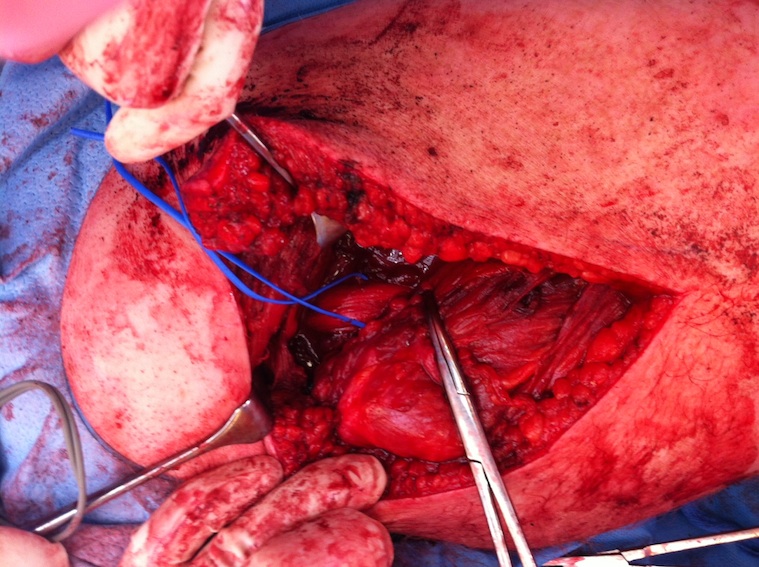

Deep dissection

- identify and preserve sciatic nerve (lateral to hamstring)

Hamstring (*) with sciatic nerve lateral to hamstring (blue vessiloop)

Identify and release proximal hamstring tendon

Stump of the conjoint tendon (*)

Expose ischial tuberosity

- superior retractor on ischial tuberosity

- medial and lateral retractors, care with sciatic nerve

- use osteotomes to create bleeding

- 2 - 3 suture anchors, double loaded